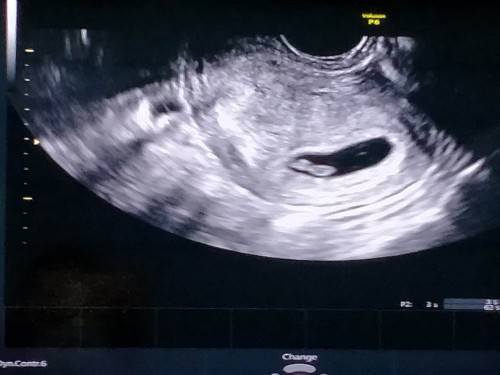

6วีค4วันเจอน้องพร้อมหัวใจคะ

ครั้งเดียวค่ะ ซาวด์ตอนนี้น้องขยับตัวด้วยหัวใจก็เต้นค่ะ